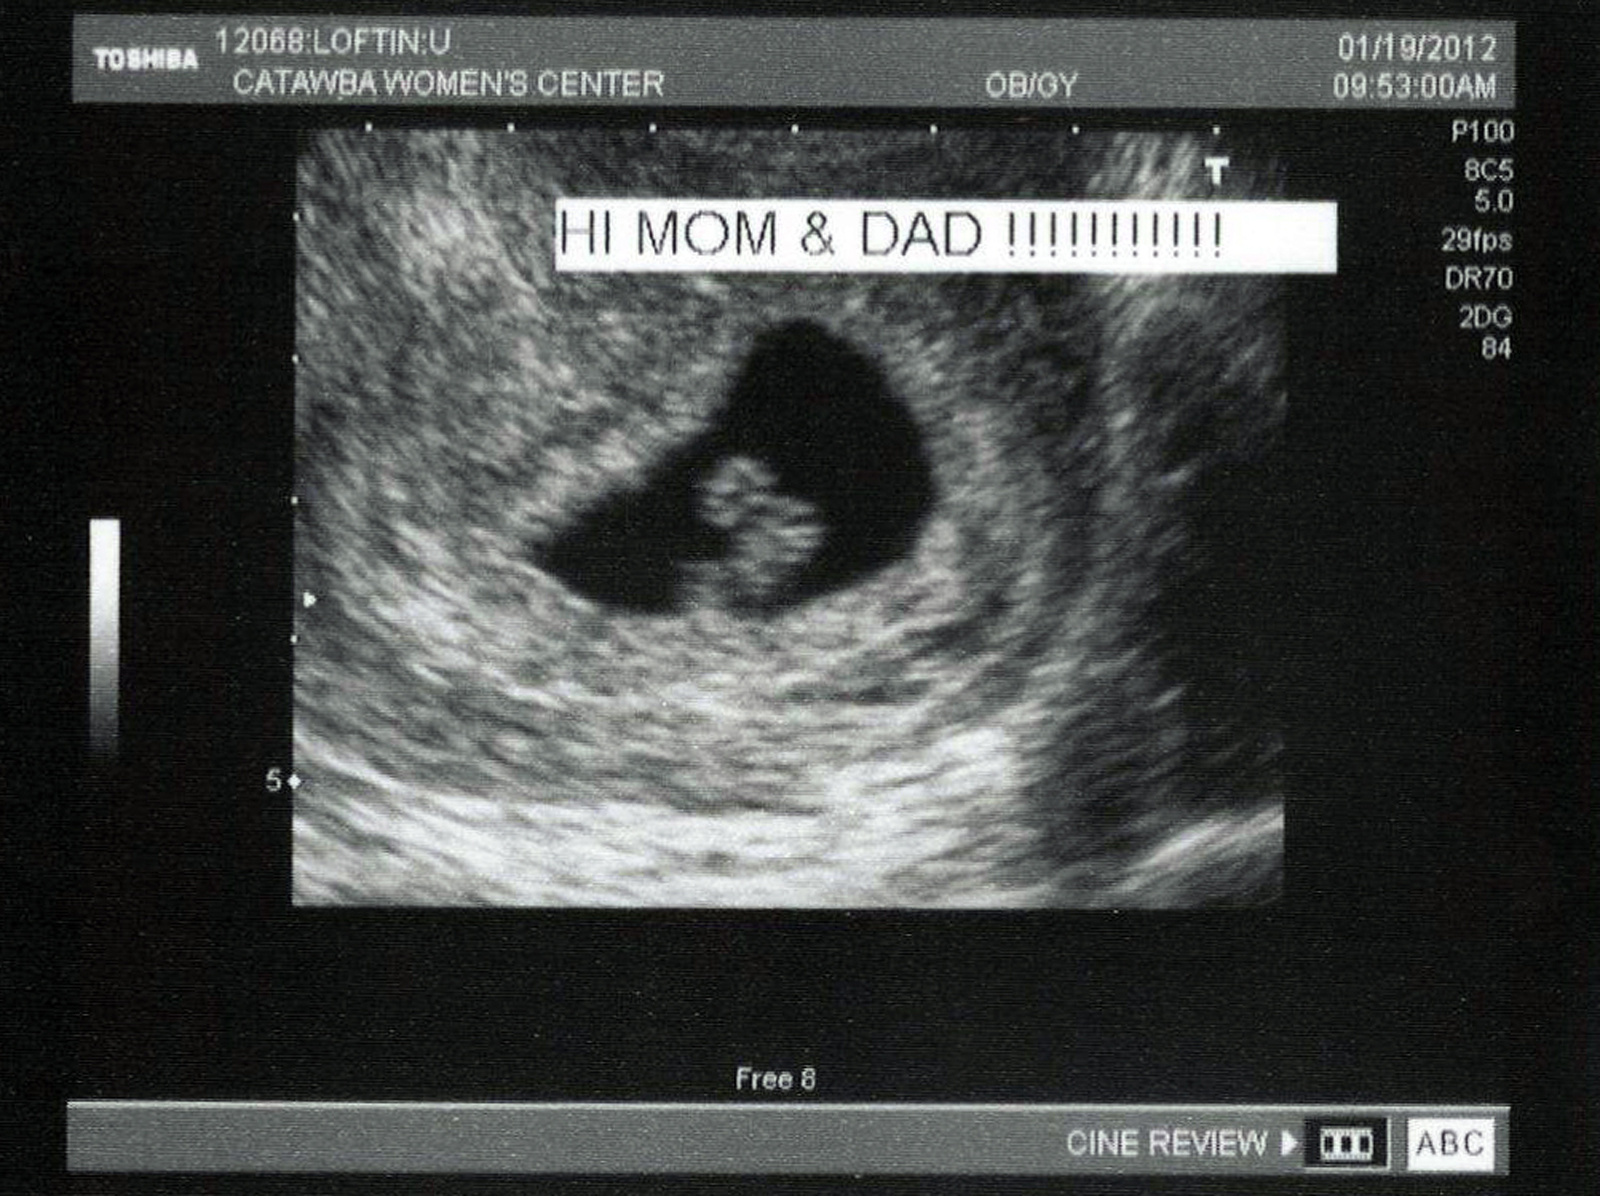

Taken at 7 weeks

These pictures are from Jan 19, 2012.